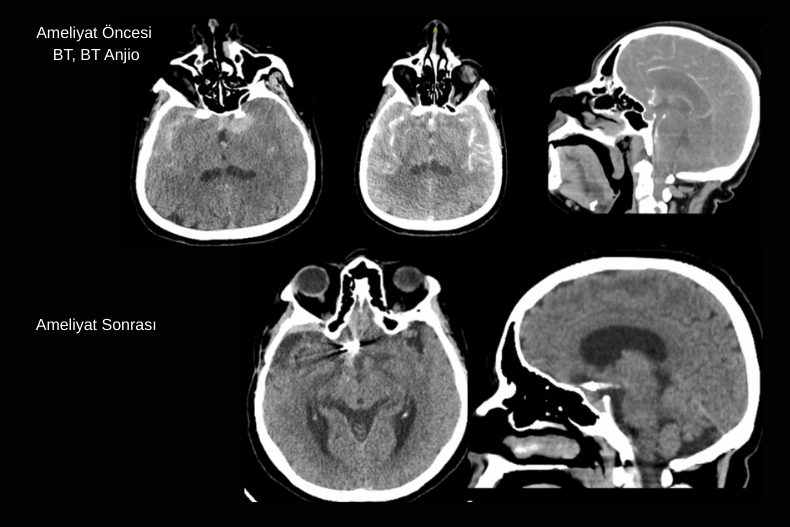

Dekompresif kraniektomi genellikle BT’de belirgin orta hat kayması (shift), bazal sisternlerde silinme ve ciddi beyin ödemine bağlı kitle etkisi görülen hastalarda uygulanır. Bu bulgular, artmış kafa içi basıncının beyin dokusunu karşı tarafa ittiğini ve beyin sapı basısı riskinin oluştuğunu gösterir. Cerrahi sırasında kafatasının bir bölümü çıkarılarak beyne genişleme alanı sağlanır ve bu sayede bası azaltılır, serebral perfüzyon korunur.

Özellikle masif akut subdural hematom olgularında hematom boşaltıldıktan sonra beyin dokusunda ciddi ödem gelişmişse kemik flep hemen yerine konulamayabilir. Bu durumda kemik geçici olarak çıkarılır ve hasta stabilize edildikten haftalar ya da aylar sonra kranioplasti ile tekrar yerine yerleştirilir. Amaç, erken dönemde beyin şişmesine karşı yeterli alan tanıyarak sekonder hasarı önlemektir.

Malign MCA enfarktı çoğu zaman tek başına geniş bir beyin yarım küresini etkilerken, bazı olgularda tabloya ICA (Internal Carotid Artery) oklüzyonu da eşlik edebilir. ICA tıkanıklığında hem MCA hem de anterior serebral arter (ACA) sulama alanları etkilenebilir ve ortaya çıkan enfarkt alanı çok daha geniş olur. Bu durum BT’de yaygın hipodens alan, belirgin beyin ödemi, ciddi orta hat kayması (shift), ventrikül basısı ve bazal sisternlerin silinmesi ile kendini gösterir. Klinik olarak hızla bilinç bozulması gelişir ve beyin sapı herniasyonu riski artar.